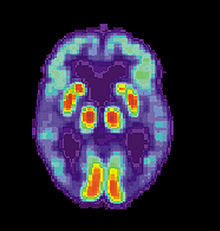

Imaging

Of the many medical imaging techniques available, single photon emission computed tomography (SPECT) appears to be superior in differentiating Alzheimer's disease from other types of dementia, and this has been shown to give a greater level of accuracy compared with mental testing and medical history analysis.[298] Advances have led to the proposal of new diagnostic criteria.[22][113]

PiB PET remains investigational, but a similar PET scanning radiopharmaceutical called florbetapir, containing the longer-lasting radionuclide fluorine-18, has recently been tested as a diagnostic tool in Alzheimer's disease, and given FDA approval for this use.[299][300]

Amyloid imaging is likely to be used in conjunction with other markers rather than as an alternative.[301] Volumetric MRI can detect changes in the size of brain regions. Measuring those regions that atrophy during the progress of Alzheimer's disease is showing promise as a diagnostic indicator. It may prove less expensive than other imaging methods currently under study.[302]